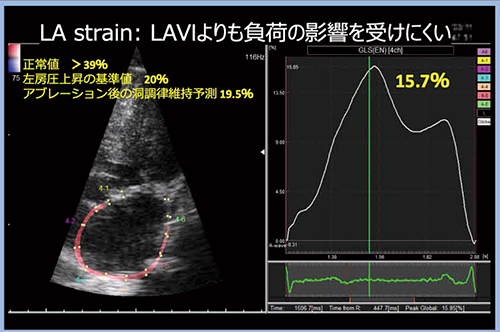

3.左房ストレインによる線維化の評価

左房リモデリングは,電気的現象としては興奮伝導遅延から低電位へと進行し,機能・構造的現象としては収縮伝導遅延からリザーバ機能およびポンプ機能の低下,左房壁肥大,左房拡大へと進行する。その背景には,組織学的現象として左房壁線維化の進行があると言われている。心房の線維化を直接診断する方法として,MRIの遅延造影による定量化法が報告され注目されているが,再現性に乏しいことが課題となっている。

一方,心エコーによる左房の線維化の指標として,Global Longitudinal Strain(GLS)が検討されている。GLSは,左室の線維化指標として知られているが,左房においても同様の研究が行われており,軽度と重度の線維化を左房ストレインにより区別できることが報告されている8)。

左房ストレインは,LAVIよりも負荷の影響を受けにくいことが特長であり,LISENDO 880LEでは左房ストレインを自動で計測することができる(図4)。GLSの正常値は>39%であるが,本症例はGLSが15.7%と低下しており,線維化が進んでいることが予測される。左房圧上昇の基準値は20%,アブレーション後の洞調律維持予測は19.5%であるため,約GLS<20%が左房ストレイン悪化のカットオフ値であると言える。また,HFpEF(LVEFが保たれた心不全)の診断における左房評価についても,構造的評価としてLAVI>34mL/m2,機能評価として左房ストレイン<20%を基準値とすることが提唱されている9)。

図4 左房ストレインの自動計測